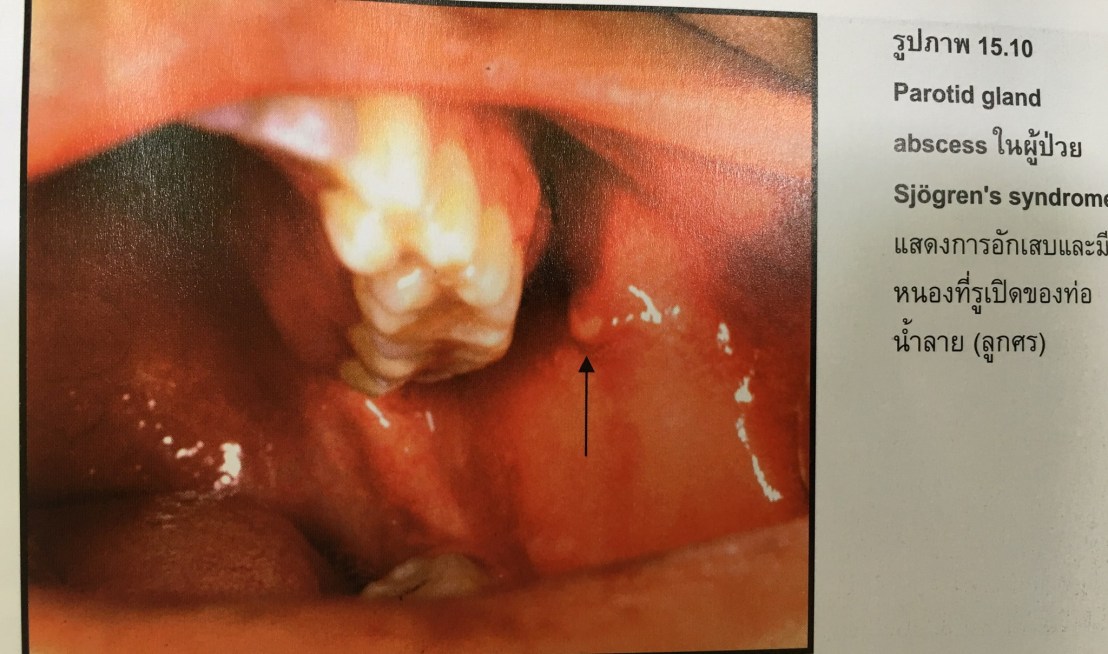

ถ้าเห็นรูปนี้ คิดว่า เราจะ Dx ว่าอะไรครับ?

มันคือความผิดปกติของต่อมน้ำลาย ดังนั้นขอให้นึกถึงสภาพของช่องปากคนไข้ที่มีน้ำลายน้อยมากๆ

Secretion จะน้อยลงทุกตัว รวมถึงน้ำตาด้วยครับ

SS คือ Sjogren’s syndrome วิธี Diff Dx ออกจากโรคของต่อมน้ำลายที่อักเสบจาก Infection